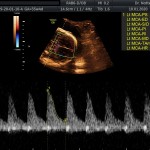

- Vitalidad y el bienestar fetal (Doopler).